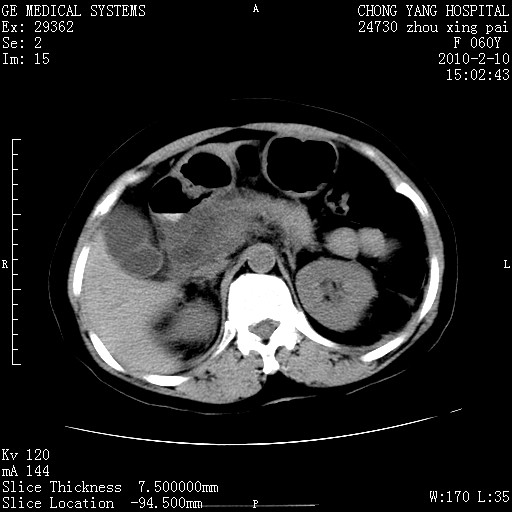

标题: CT24682:F60Y 腹痛 其它不详 [打印本页]

标题: CT24682:F60Y 腹痛 其它不详

胆总管末端梗阻!结石?肿瘤?建议增强!必要时行ercp!

胆总管末端梗阻!结石?胰腺影增粗,以胰腺头部为著,胰周看见渗出影,双侧胸腔积液,(胸膜反应)考虑胰腺炎。

1)胆总管末端梗阻,不排除结石所致可能。2)胰腺炎。3)慢性胆囊炎可能。4)左侧输尿管上段扩张。5)少量腹水。6)双侧少量胸腔积液,伴两下肺部分肺萎陷。

1)胆囊炎。2)胆源性胰腺炎。3)右肾周筋膜增厚,肾旁前间隙积液。4)左侧输尿管上段扩张。5)少量腹水。6)双侧少量胸腔积液,伴两下肺部分肺膨胀不全。

急性胰腺炎所致胆总管扩张!

1)胆总管末端梗阻。2)胰腺炎。3)慢性胆囊炎可能。4)左侧输尿管上段扩张。5)少量腹水。6)双侧少量胸腔积液,伴两下肺部分肺萎陷。